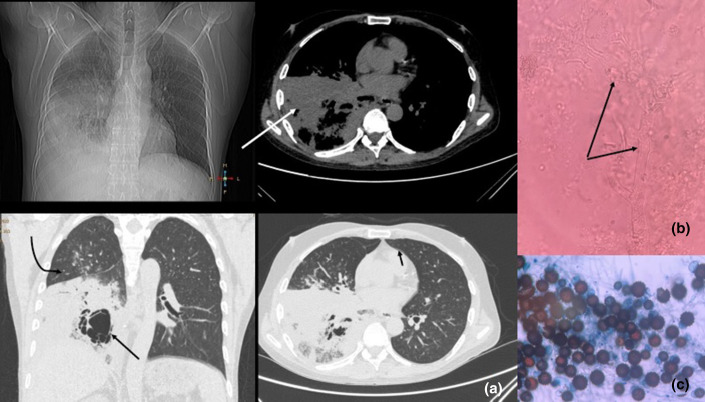

Introduction: Rhizopus homothallicus is an emerging pathogen that causes pulmonary mucormycosis.

Case presentation: We report a case of pneumonia caused by R. homothallicus in a 54-year-old type 2 diabetic patient. The organism was isolated from bronchoalveolar lavage fluid and preliminarily identified by fungal morphology and finally by sequencing of the internal transcribed spacer region.

Conclusion: Mucormycosis may be associated with cavitary lung lesions against a backdrop of poorly controlled diabetes or other immunosuppressed states. Pulmonary mucormycosis may have variable clinical and radiological presentations. Therefore, strong clinical suspicion and prompt management can address the high fatality associated with the disease.